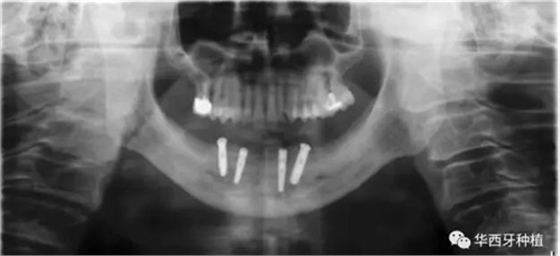

吳教授特別針對手術(shù)難度更大的all-on-four修復(fù)做了詳細的關(guān)于概念、設(shè)計、操作、修復(fù)的描述,首先是針對難度最大的手術(shù)環(huán)節(jié),就解剖、微創(chuàng)操作分別加以闡述。將他自己在臨床工作中的寶貴經(jīng)驗分享給了大家。

對于傳統(tǒng)的all-on-four術(shù)式,吳教授加入了微創(chuàng)的指導思想,設(shè)計時同樣加入數(shù)字化三維重建與修復(fù)一體化設(shè)計,增加了手術(shù)的可控性,同時極大減輕了患者的創(chuàng)傷程度,縮短了修復(fù)周期。

演講結(jié)束前,吳教授再次提到了數(shù)字化對口腔全口牙缺失種植修復(fù)一體化的重要性,構(gòu)建一體化的數(shù)字化種植修復(fù)流程,不僅能輔助手術(shù),更是簡化修復(fù)和確保遠期療效的一把利器。